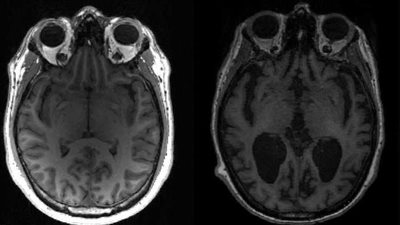

متلازمة غيلان باريه (GBS)، أحد الأمراض العصبية النادرة التي تصيب الإنسان فجأة دون مقدمات وليس لها أسباب محددة. ما هي متلازمة غيلان باريه؟ متلازمة غيلان باريه هي اضطراب عصبي نادر، حيث يهاجم الجهاز المناعي للجسم الجهاز العصبي المحيطي عن طريق الخطأ. يمكن أن تؤدي هذه الحالة إلى الضعف والخدر، وفي الحالات